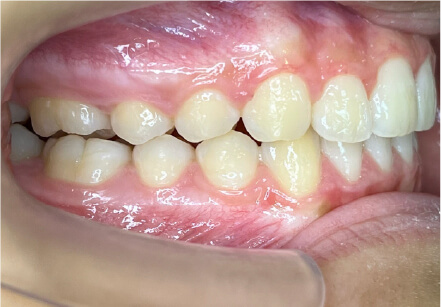

叢生の症例

8歳

女性

相談内容

前歯がでている、前歯が噛み合っていない

カウンセリング・診断結果

上下叢生、顎が狭いのでクリアコレクトで拡大配列+トレーニングで進めてく

治療内容・方法

全額アライナー矯正 クリアコレクト

術後の経過・現在の様子

リンガルアーチ使用

治療のリスク

痛み・歯根吸収・歯肉退縮・虫歯・後戻り

費用・治療期間

924,000円、8ヶ月